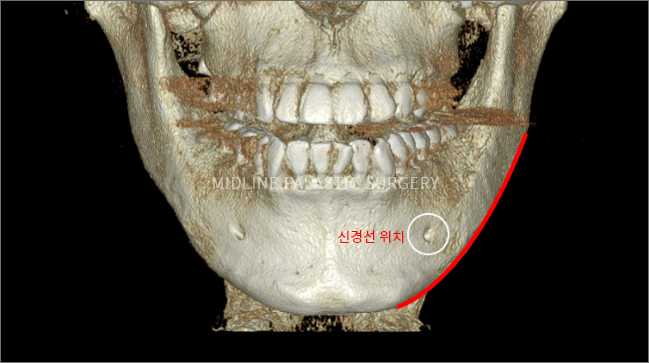

한 번에 길게 곡선형태의 절골술을 하여야 이차각이나 신경 손상 등의 부작용을 줄이고,

수술 시 정면 효과를 최대한으로 끌어낼 수 있도록 입안 절개를 통한 올라운드 사각턱 수술을 고집하고 있습니다.

01. 라운딩 방식으로 남긴 Fix-Zone의 지지대 역할

각자의 피부 상태, 뼈의 상태를 진단하여 남은 지방과 근육을 지지할 정도의 뼈의 부피를

0.01mm 단위까지 계산하여 절단면에 rounding을 주어 Fix-Zone을 남기고 사각턱 절골술을 진행하게 됩니다.

CT 촬영

3D-CT로 촬영한 데이터를 기반으로 얼굴뼈

전체를 정밀하게 분석하여 보다 안전하고

정확한 수술 계획이 가능합니다.